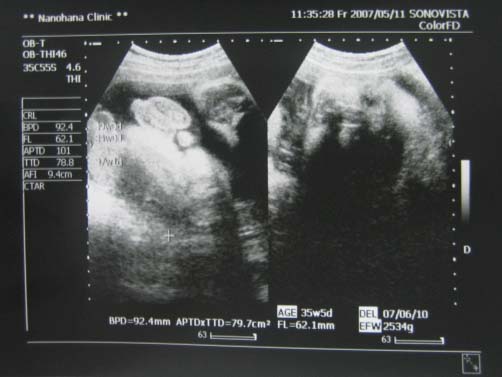

ベビちゃんは元気で、エコー中も暴れていた様子。

先生も「よく動いているみたいですね」って。

今回で2534グラムでした。

体は週数どおりのサイズなのに、頭が一週分デカイサイズらしいです

今回はこんな写真をもらいました

向かって右は顔。(相変わらずわかりにくいですが、右側がおでこで左側が口です)

で、向かって左はおまたの写真。

そうで~す!

おちんちんですって。

男の子だということは、以前に聞いていたのですが、写真でもらったのは初めて